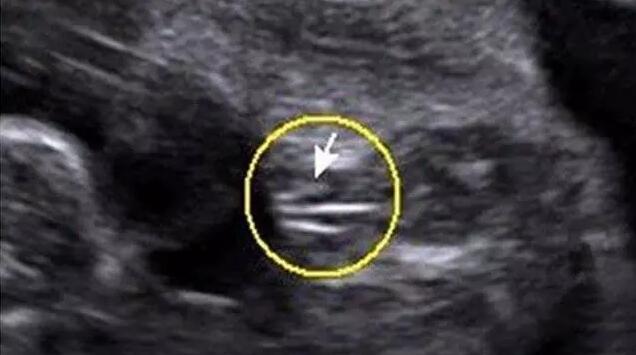

四维彩超女宝宝特征如下

女宝B超图的特征是“三条白线”,当然最好的角度还是从下方来看。如果没有看到三条白线,那么就瞪大眼睛看双腿之间突出的部分,如果特征为两边鼓中间凹,那就基本是女宝了。如下图所示。

三条白线